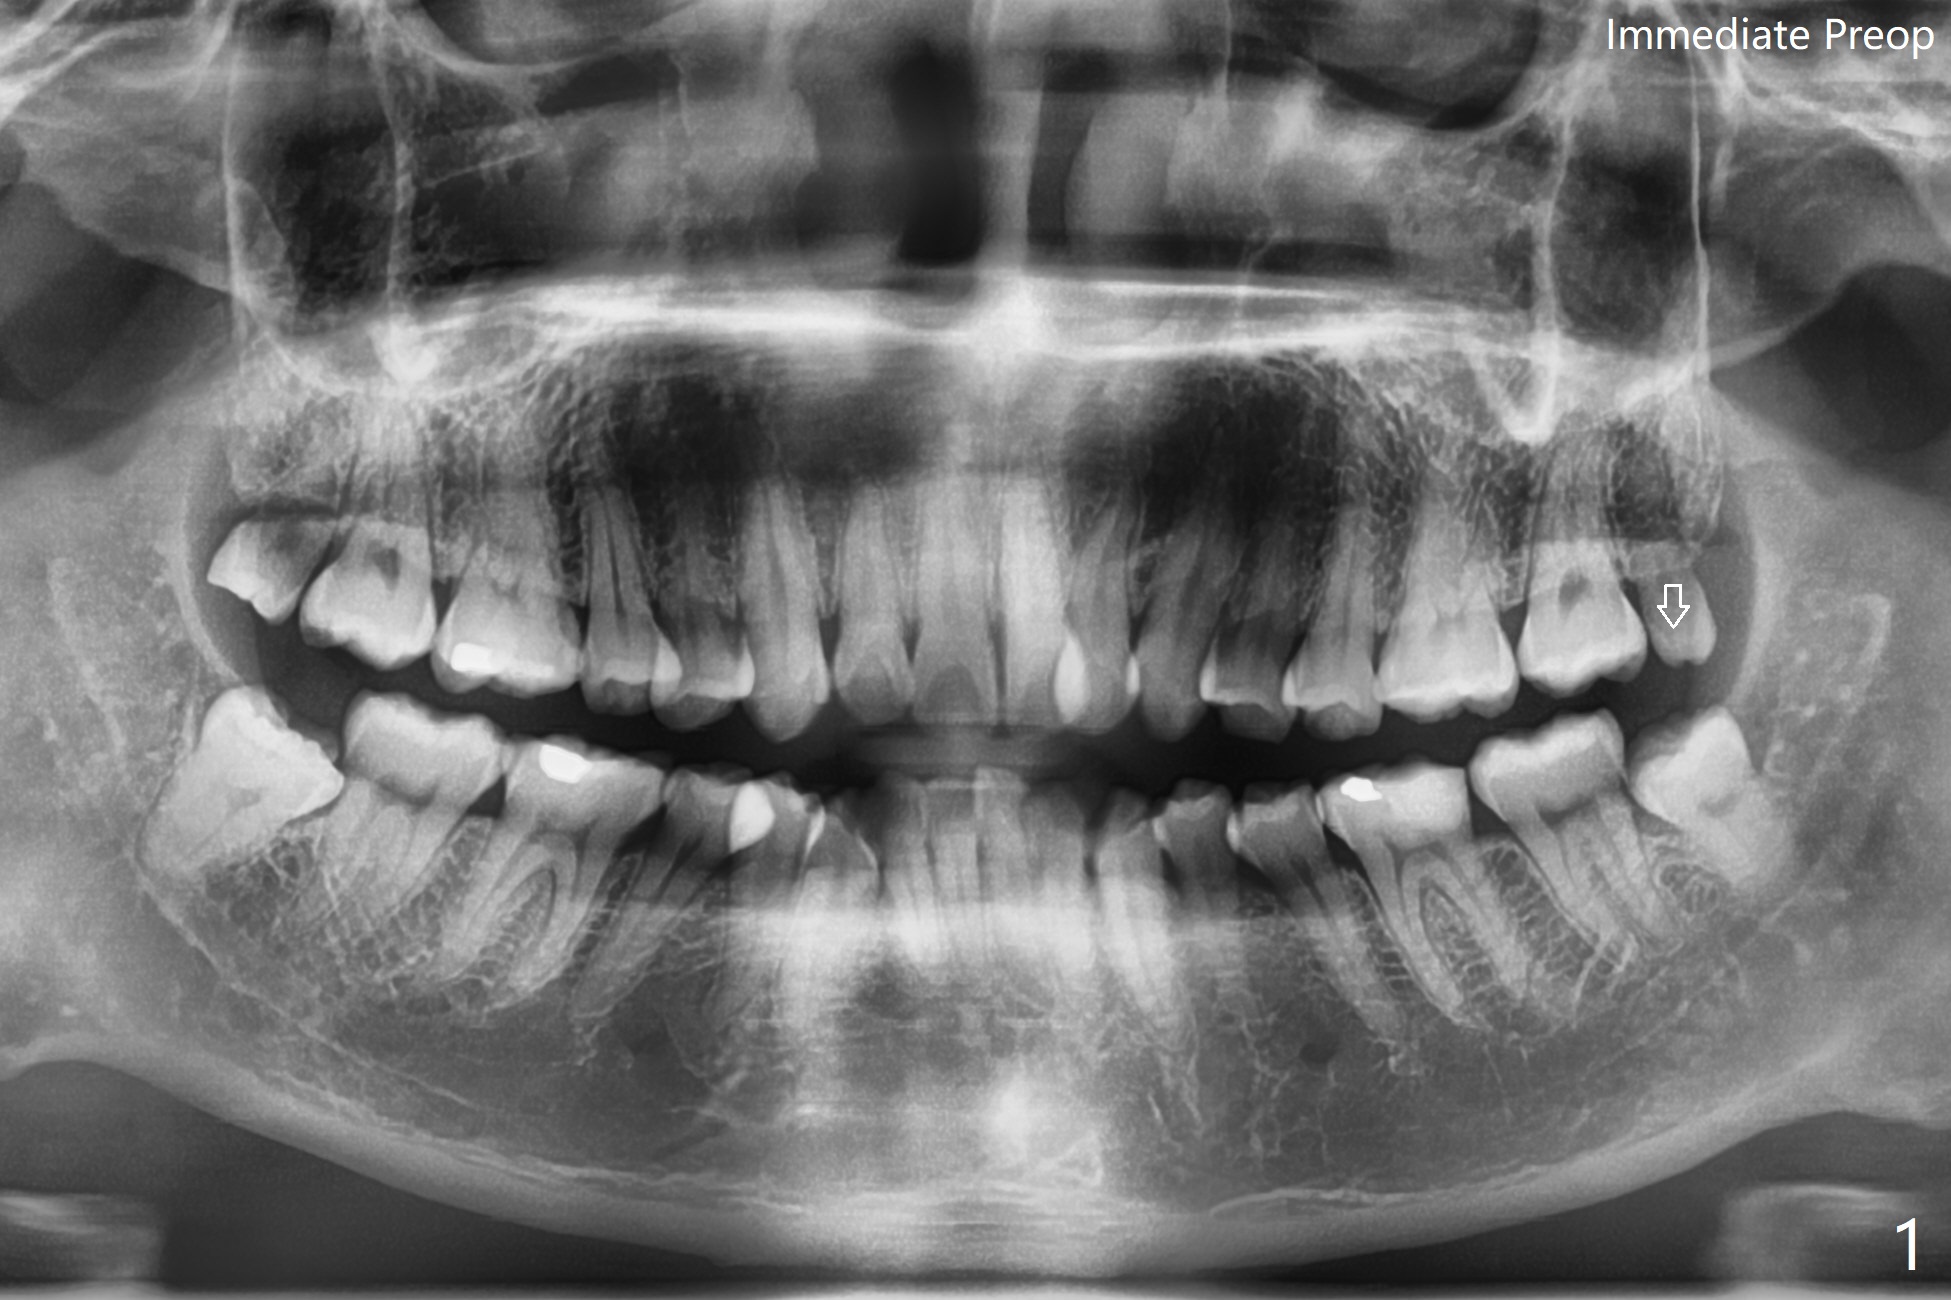

#17 Traumatized by #16

A 30-year-old man complains of chewing pain at #17. The distal gingiva seems to have been traumatized (adhesion) by the opposing 3rd molar (Fig.1 arrow). The tooth is out following sectioning twice with the socket inserted with Osteogen plug (Fig.2). Return to Plug Xin Wei, DDS, PhD, MS 1st edition 05/19/2021, last revision 05/20/2021